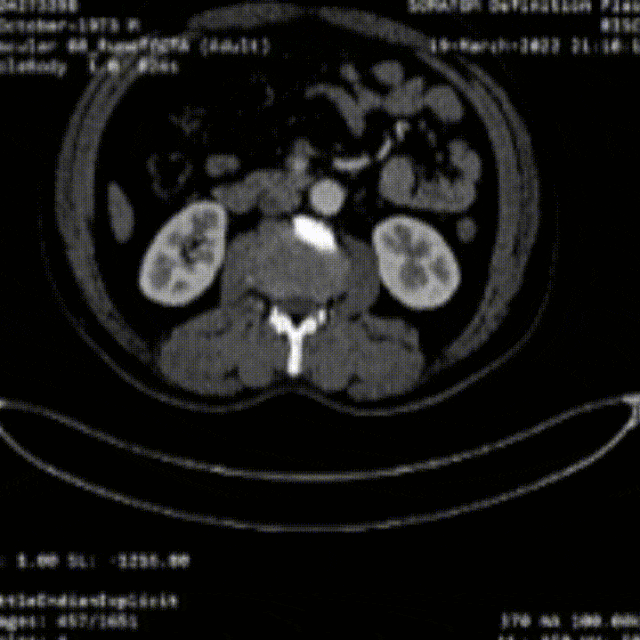

★病例1

28岁男性,急性复杂型B型AD,急诊TEVAR治疗